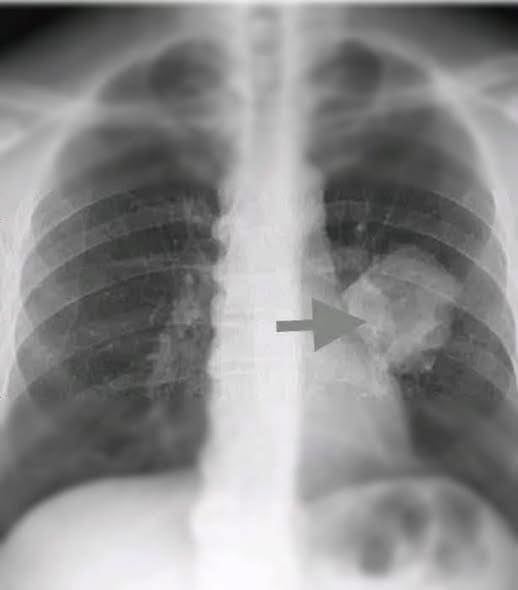

In a startling development that has caught the attention of the international medical community, a team of fully vaccinated researchers has reported the discovery of a previously unidentified type of cancer. Early findings suggest that this disease is spreading silently across multiple continents, posing a challenge to early detection and treatment